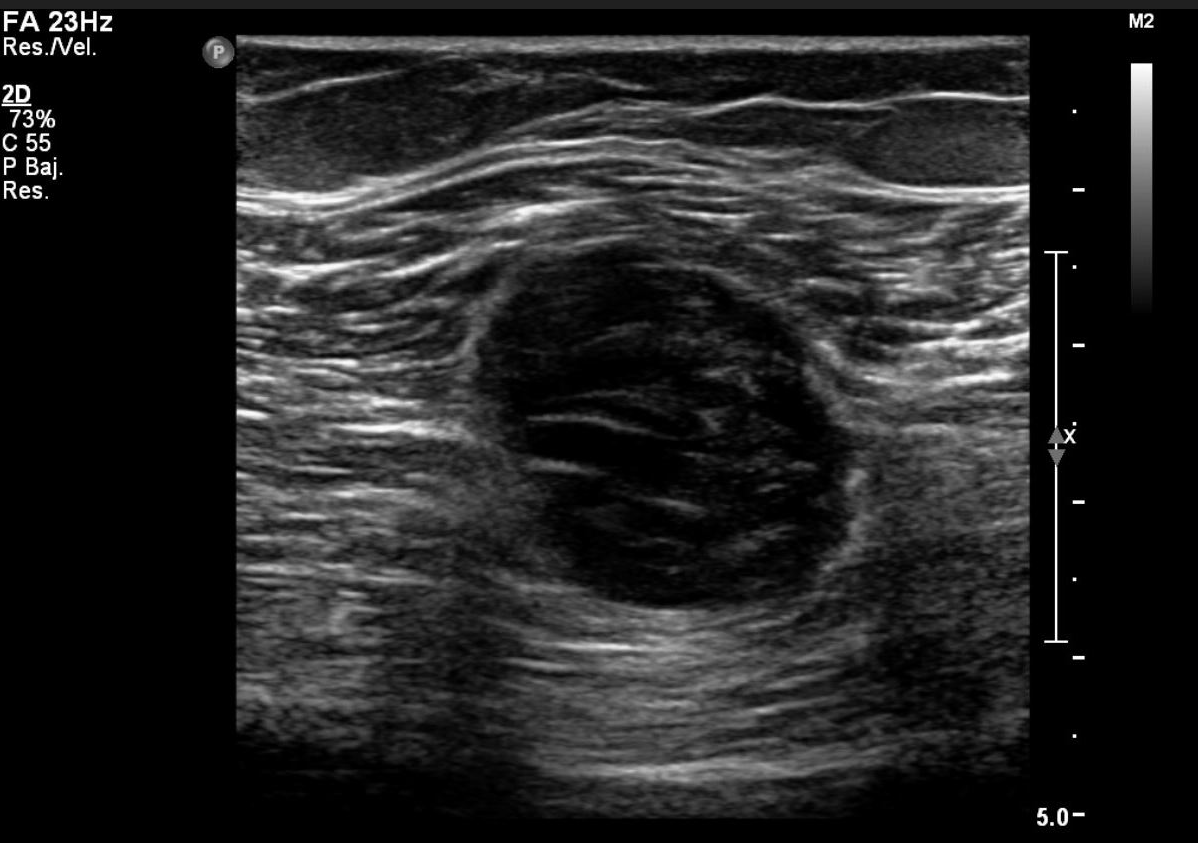

Ecografía modo B